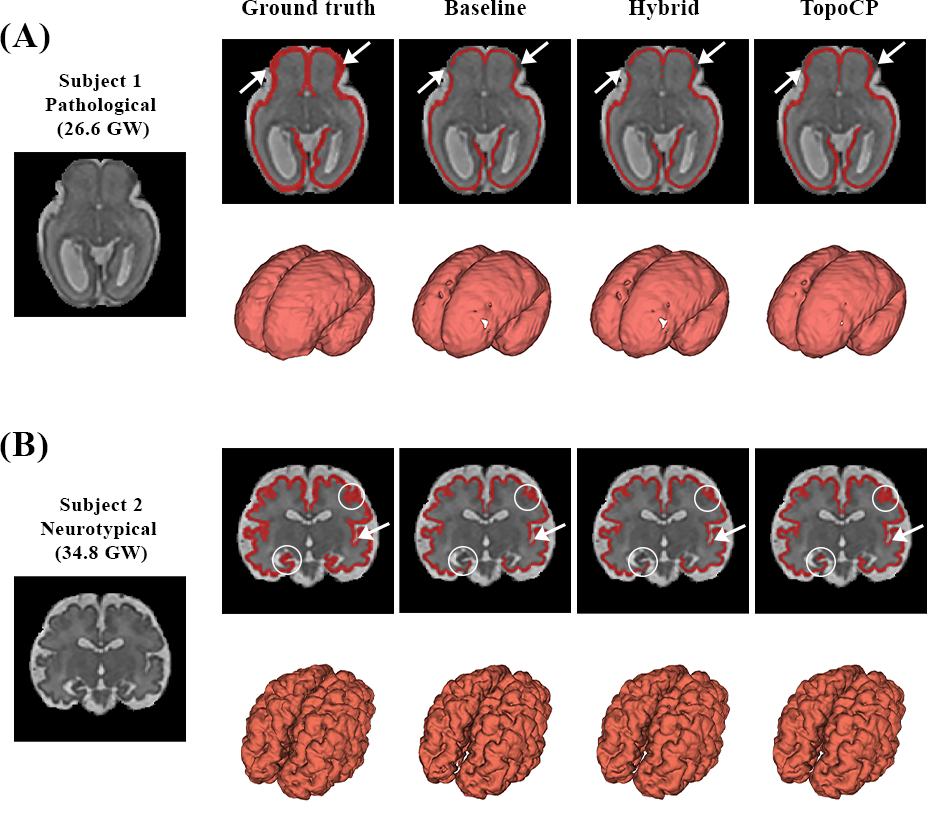

Figure 10 illustrates the accuracy of the fetal CP segmentation for a pathological subject of 26.6 (Subject 1) and a neurotypical subject of 34.8 (Subject 2) weeks of GA. The topologically corrected ground truth and the three configurations segmentation with Baseline, Hybrid, and TopoCP, are compared. Qualitative 2D assessment (top rows) of the segmentation are presented as an overlay on the T2w image on an axial, respectively coronal, view for Subject 1, respectively Subject 2. Additionally, 3D rendering of the CP segmentation are presented in the bottom rows. Overall, we observe that all configurations generates a thinner ribbon than the corrected ground truth. Specifically, TopoCP presents fixed cortical connections that are broken in the Baseline and Hybrid segmentations (white arrows). The CP TopoCP segmentation 3D rendering seems to present less bores than the two reference configurations Baseline and Hybrid. In particular, the segmentation appears, equivalently for the young and the old fetuses, more challenging, for all methods, in the lower parts of the frontal and temporal lobes, although TopoCP seems to exhibit a more sensitive segmentation in these areas. TopoCP appears to be more sensitive to the complexity of the CP morphology in older fetuses. White circles evidence in Subject 2 an improved segmentation in the hippocampal area and the depth of a gyrification. White arrows show area where the topological correctness recovered with TopoCP, compared to the Baseline. In Subject 1, two connections are fixed in the frontal lobe, although one of them is already fixed in the Hybrid configuration.

Refer to caption